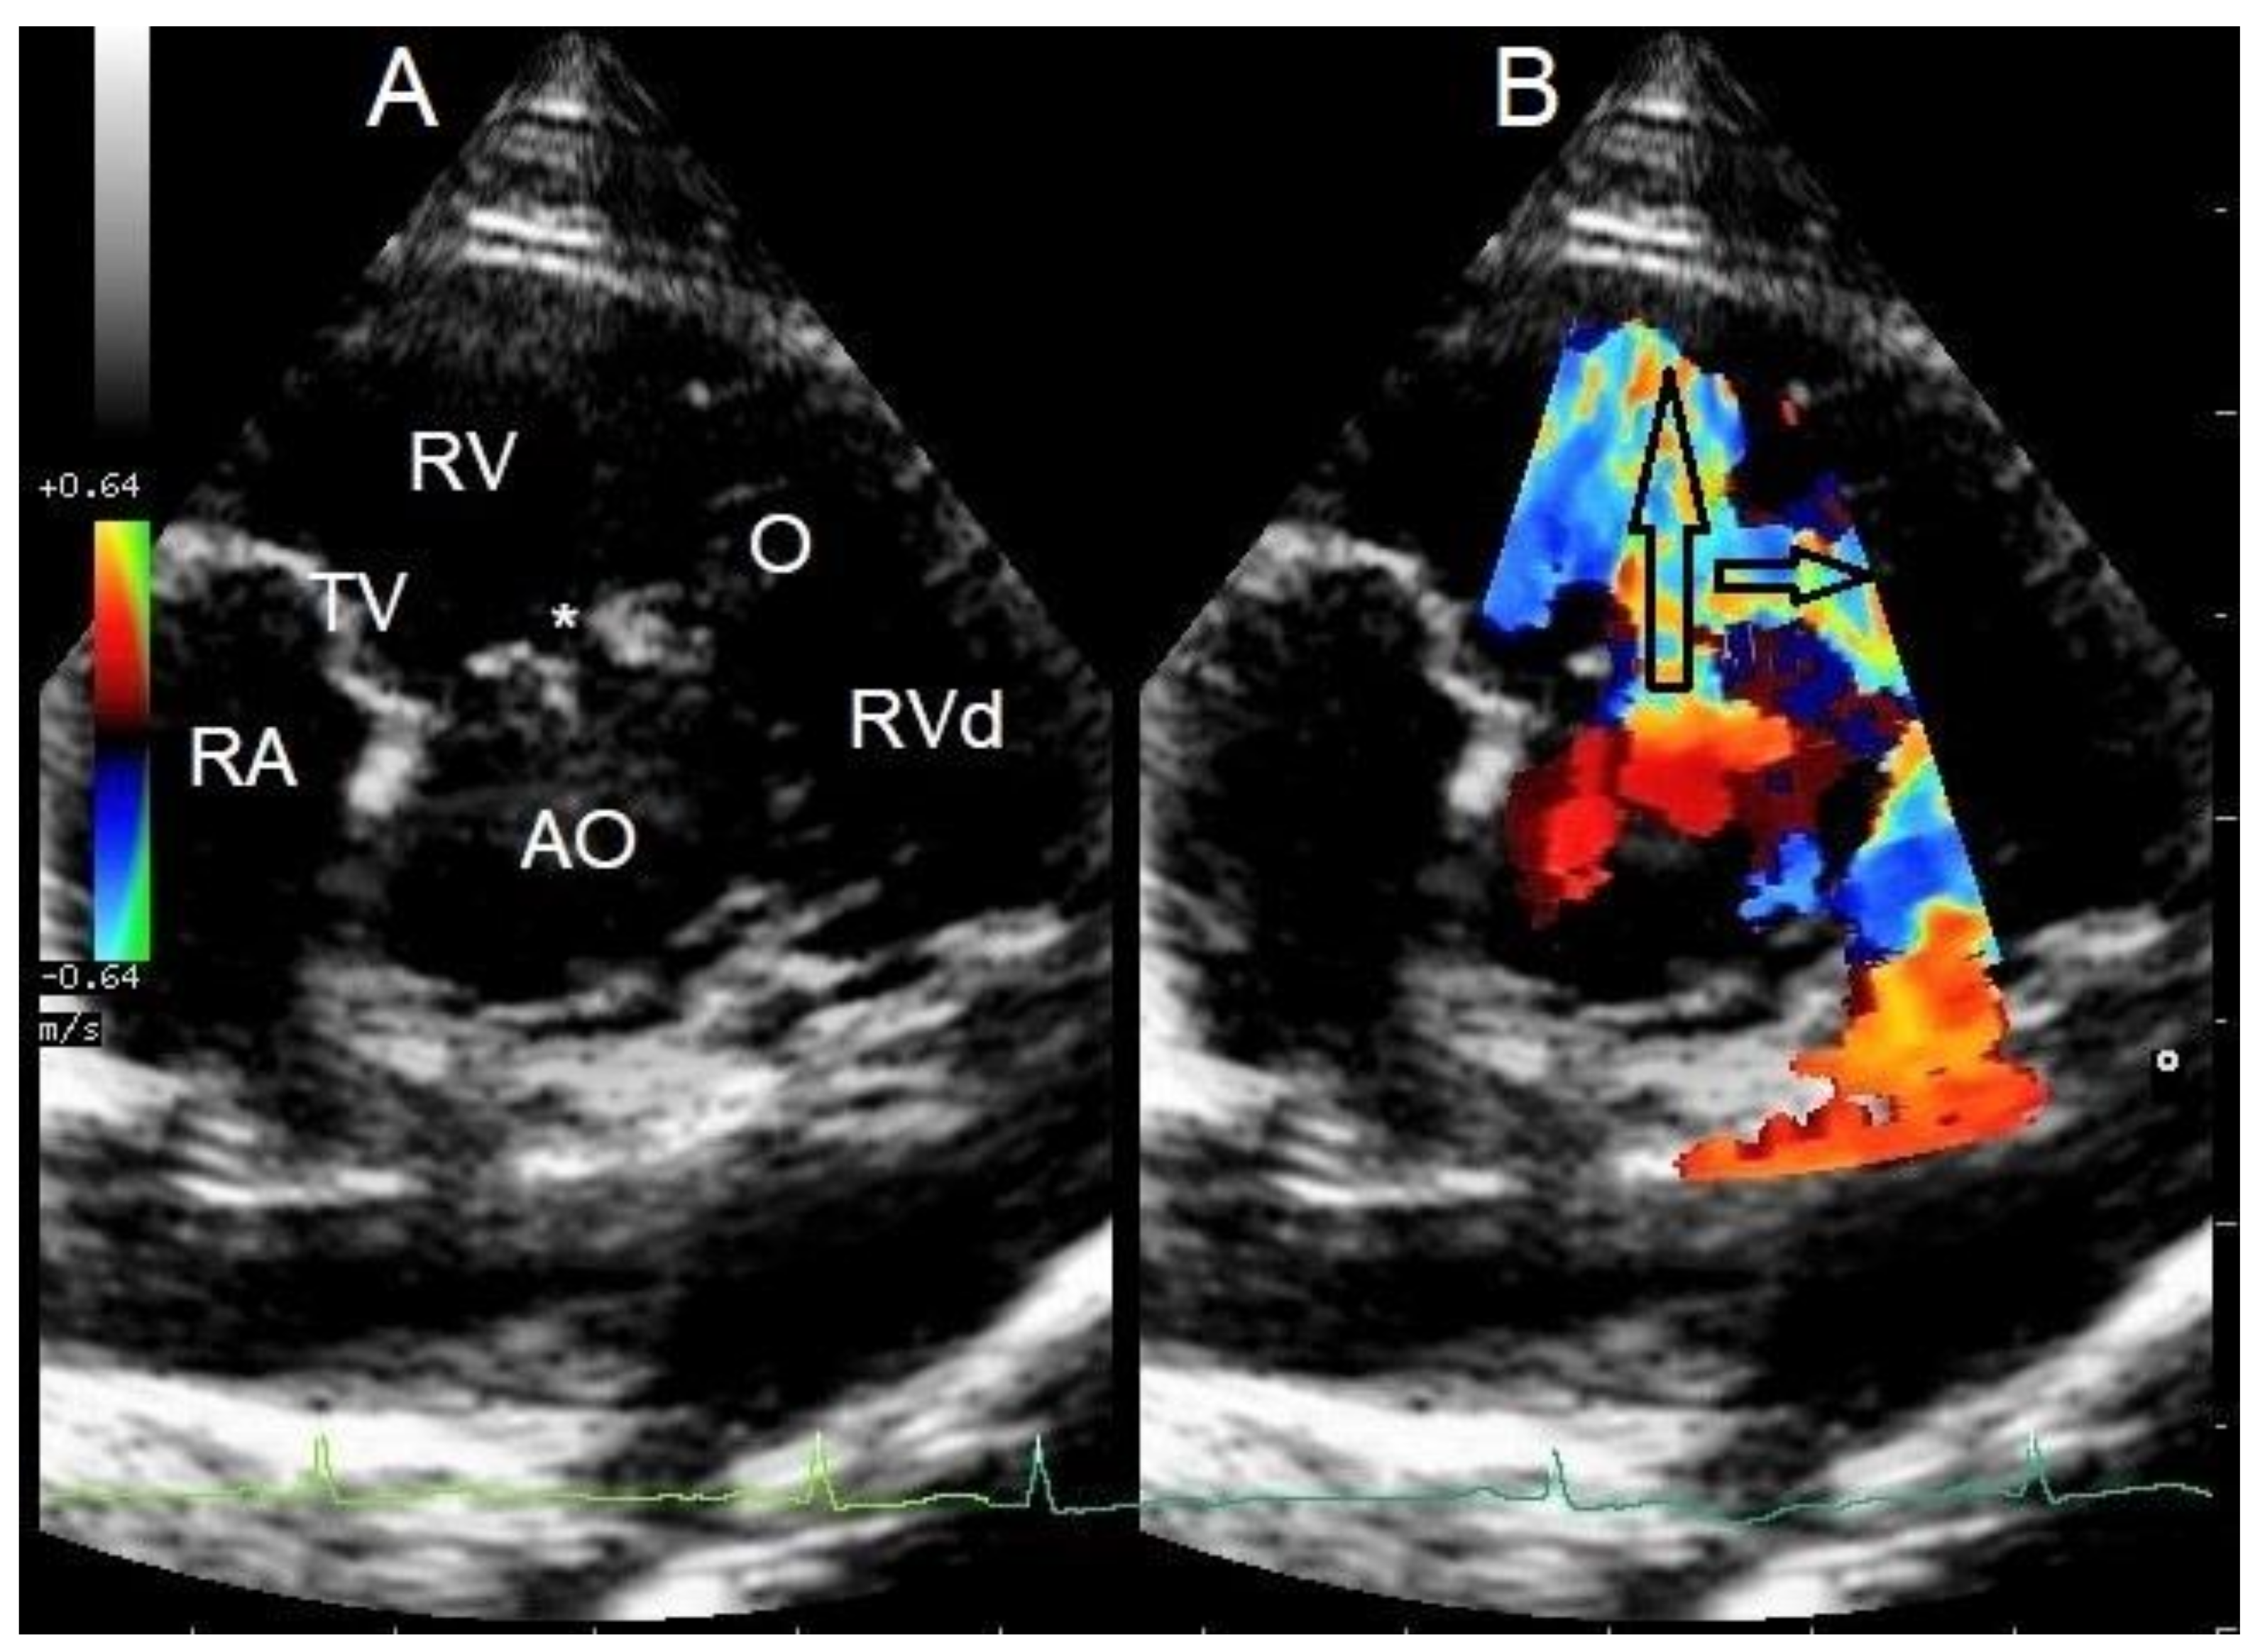

The breeder’s veterinarian found a murmur at a screening health examination at 10 weeks of age and referred the pup to a cardiologist for murmur evaluation. The puppy was free of clinical signs at that time. The cardiologist documented a systolic murmur with the point of maximal intensity on the right hemithorax and a murmur intensity of 5 out of 6. Echocardiography revealed a congenital small perimembranous left-to-right shunting VSD just underneath the aortic valve and with the right ventricular opening adjacent to the tricuspid valve (Figure 1). No echocardiographic signs of left ventricular volume overload or pulmonary hypertension were noted. In addition, localized muscular hypertrophy was noticed just distal to the VSD in the right ventricle. Continuous wave Doppler interrogation of blood flow through the VSD revealed left-to-right shunting with an estimated pressure difference between the ventricles of 64 mmHg. Continuous wave Doppler interrogation of the right ventricular outflow tract over the right ventricular obstructive lesion revealed a pressure gradient of 30 mmHg. The muscular band divided the right ventricle in a high-pressure and a normal-pressure compartment. The VSD connected the left ventricle to the high-pressure compartment of the right ventricle. Normally, no pressure gradient would be measured in the right ventricle. A left-to-right shunting restrictive VSD without right-sided pathology would typically be associated with a pressure gradient of 80–120 mmHg [1,2,3].

Figure 1. Cross-sectional echocardiographic images at the level of the heart base from the standard right parasternal short axis view performed at 10 weeks of age. (A) Two-dimensional image shows a small ventricular septal defect (*) close to the aortic (AO) and tricuspid valves (TV) and a localized muscular band in the right ventricle (O) just distal to the ventricular septal defect. RA—right atrium, RV—right ventricular chamber proximal to the obstruction, RVd—right ventricular chamber distal to the obstruction (B) Color Doppler image of the same view as in Figure 1A shows two high-velocity jets in the right ventricular chamber. The jet indicated by the large, vertically positioned arrow is caused by the left-to-right shunting ventricular septal defect, and the jet indicated by the smaller, horizontally positioned arrow is caused by the right ventricular intraluminal obstruction (O). The arrows also indicate the origin and direction of abnormal blood flow.